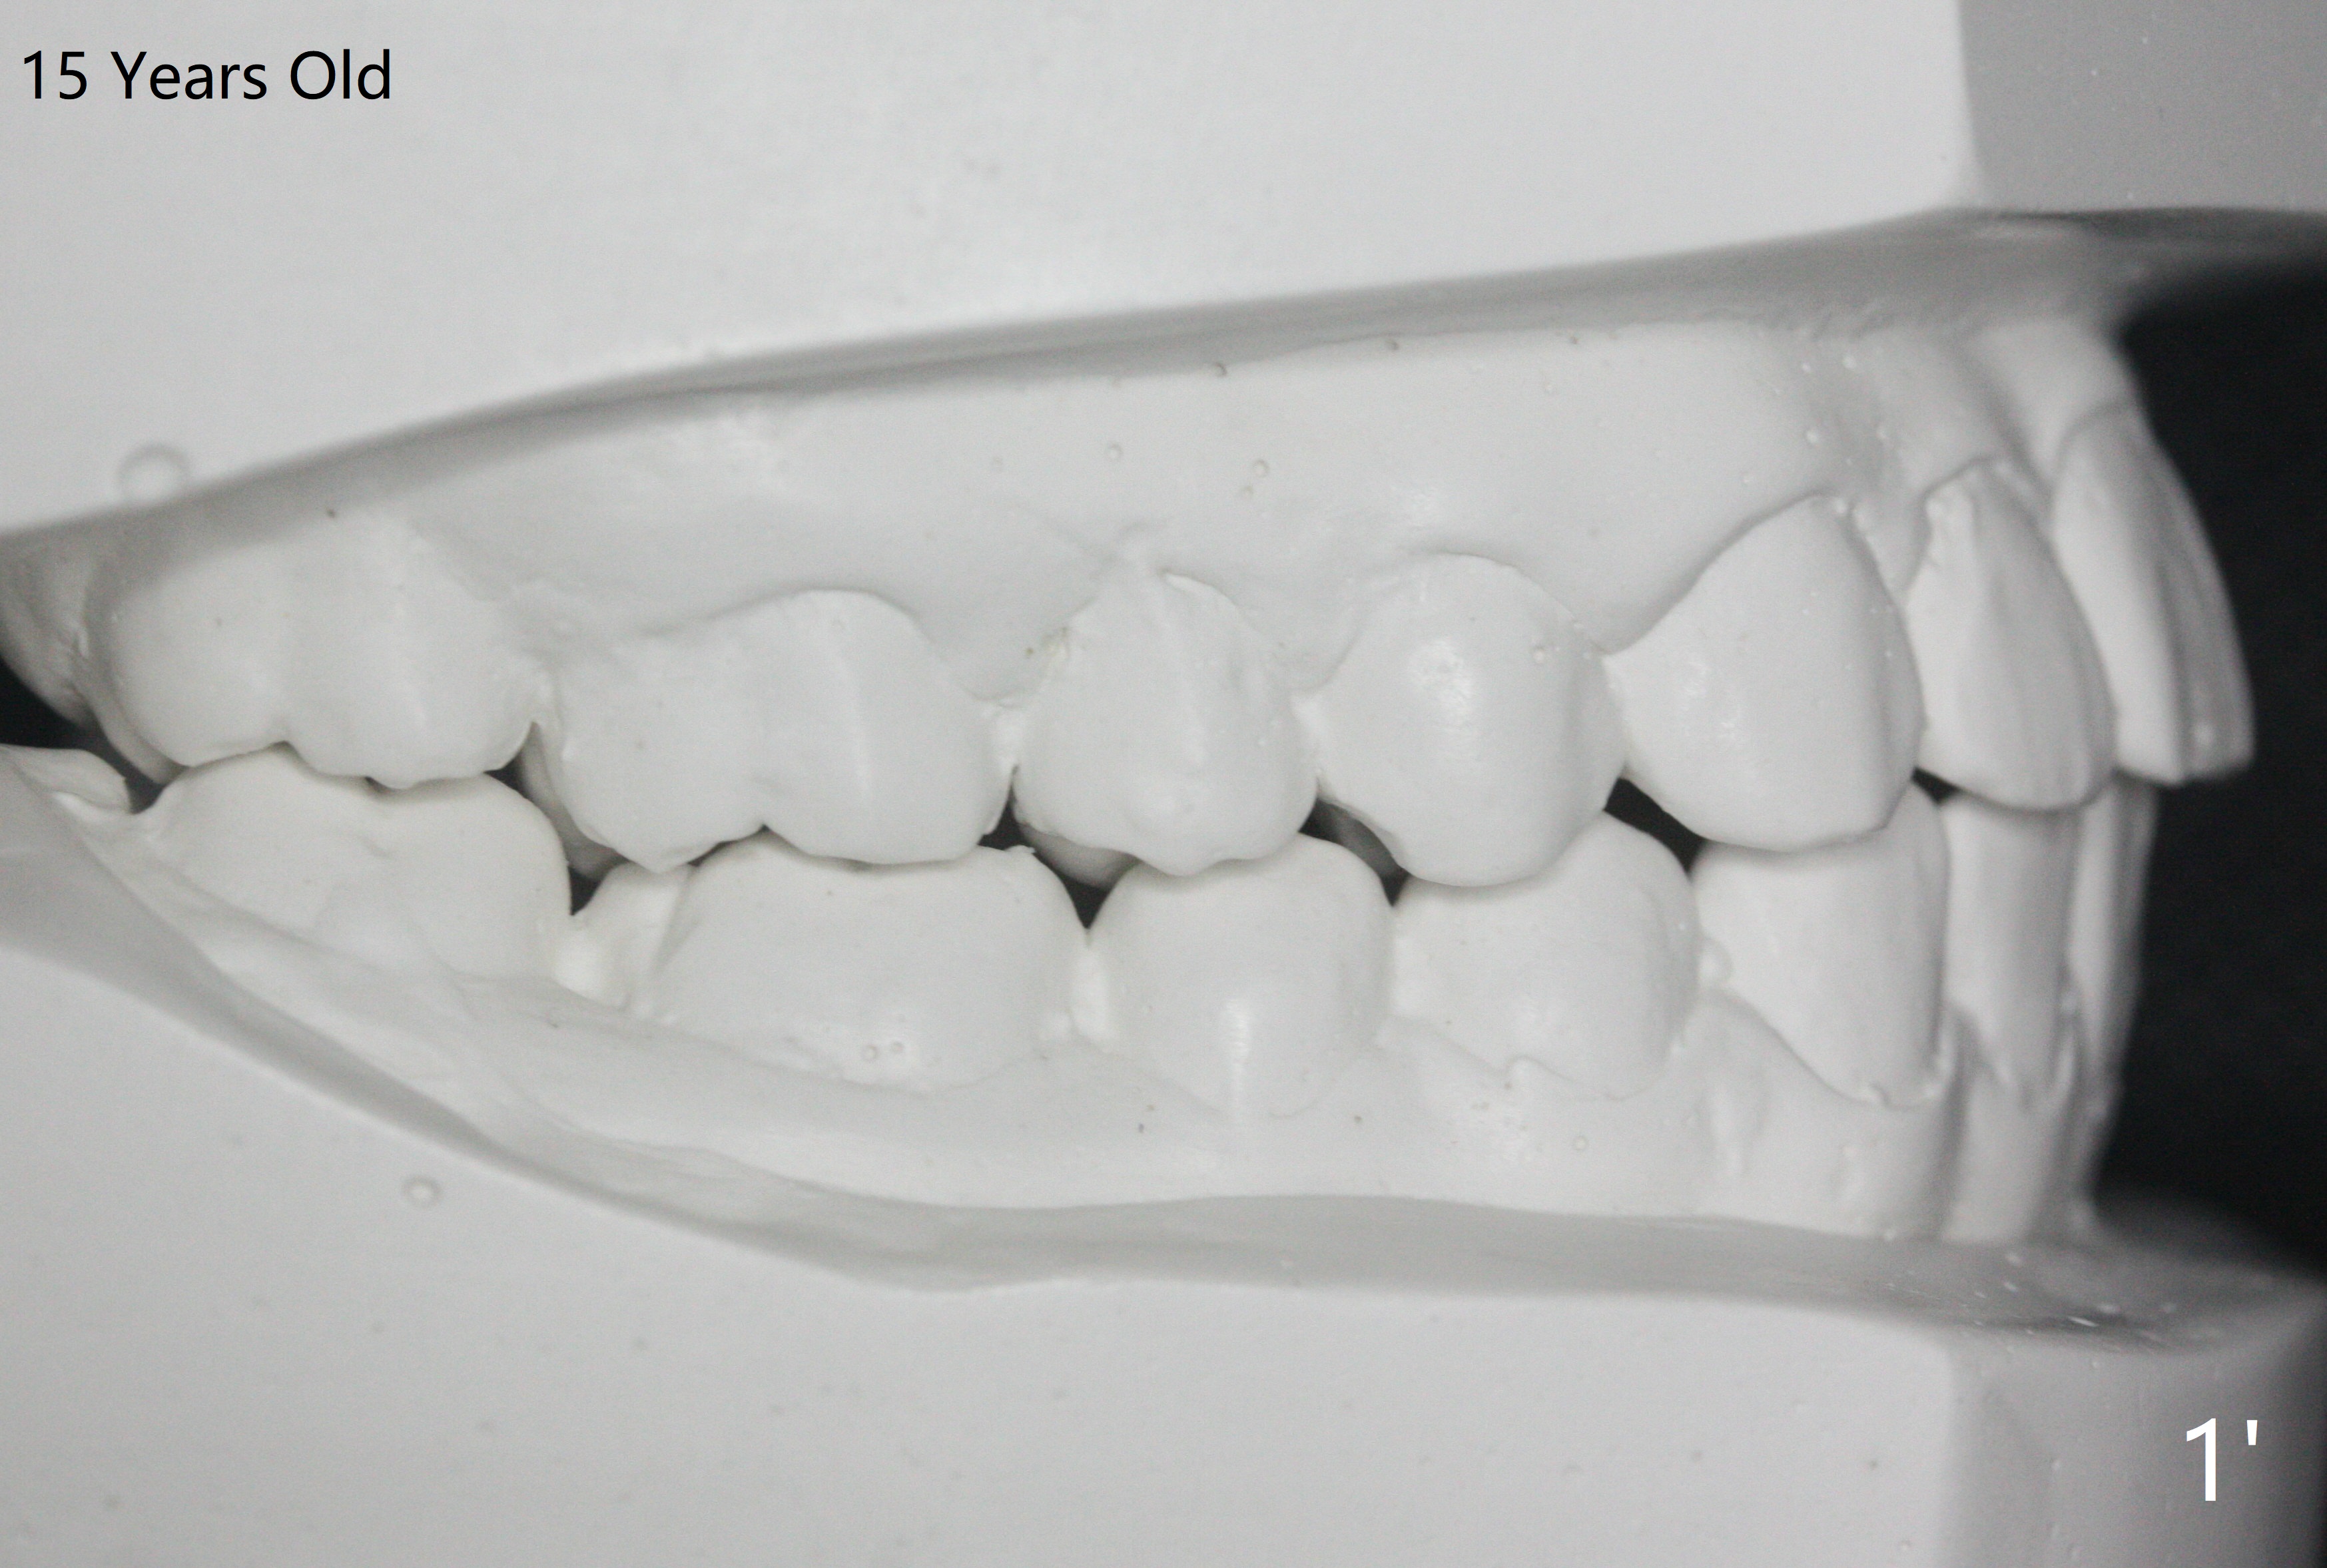

A 12-year-old woman has severe crowding including UL7 impaction (Fig.1-5), finishes non-extraction orthodontics at the age of 15 (Fig.1'-5') and returns for retainer remake at 19 (Fig.1''-5''). Four years post debanding, UL7 (Fig.4') seems to improve its position (Fig.4'').